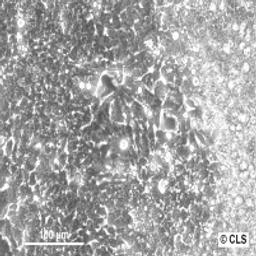

Human Colon Adenocarcinoma cell line LoVo

Morphology: epithelial

Growth Properties: monolayer, adherent